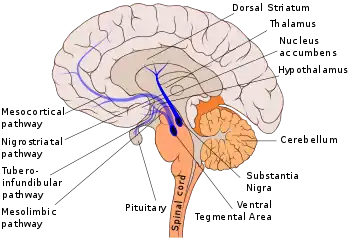

المسار السوداوي المخططي أو الحزمة السوداوية المخططة (بالإنجليزية: Nigrostriatal pathway) هو مسار دوباميني الفعل يربط الجزء المكتنز في المادة السوداء (SNc) مع الجسم المخطط (أي النواة الذنبية والبطامة). وهو أحد المسارات الدوبامينية الكبيرة الأربعة في الدماغ، وله دور محدد في إنتاج الحركة، بصفته جزءا من نظام يسمى الحلقة الحركية للعقد القاعدية. العصبونات دوبامينية الفعل الخاصة بهذا المسار تشتبك مع عصبونات شائكة متوسطة غاباوية الفعل (MSNs) تعرف كذلك بعصبونات الامتداد الشائكة (SPNs).[1][2]

![]() المسار السوداوي المخططي ظاهر هنا بأزرق متوسط الغمق، ويربط بين المادة السوداء والجسم المخطط المسار السوداوي المخططي ظاهر هنا بأزرق متوسط الغمق، ويربط بين المادة السوداء والجسم المخطط | |